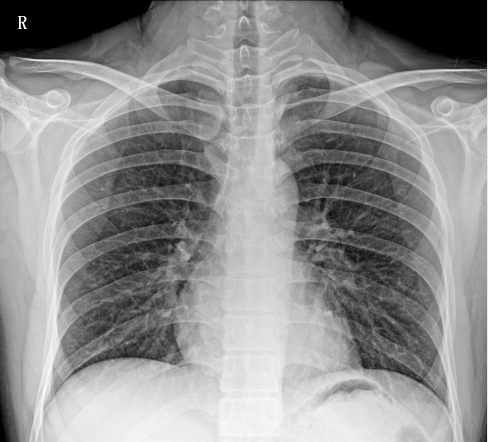

移動(dòng)DR相比只能固定作業(yè)的固定DR相比,移動(dòng)DR因其便攜性、可移動(dòng)性、操作靈活、擺位方便、占地面積小等優(yōu)勢(shì),成為ICU、發(fā)熱門診、防疫病區(qū)最為緊急采購的需求設(shè)備。在此次新冠治療中,肺炎影像學(xué)診斷是新型冠狀病毒感染的重要判斷標(biāo)準(zhǔn)之一,CT、DR等醫(yī)學(xué)影像檢測(cè)設(shè)備發(fā)揮了重要作用。因此,移動(dòng)DR被列入國家《重大疫情救治基地應(yīng)急救治物資儲(chǔ)備清單》。下面就大家介紹一下普愛PLX5100型移動(dòng)DR的產(chǎn)品性能和工作站功能。